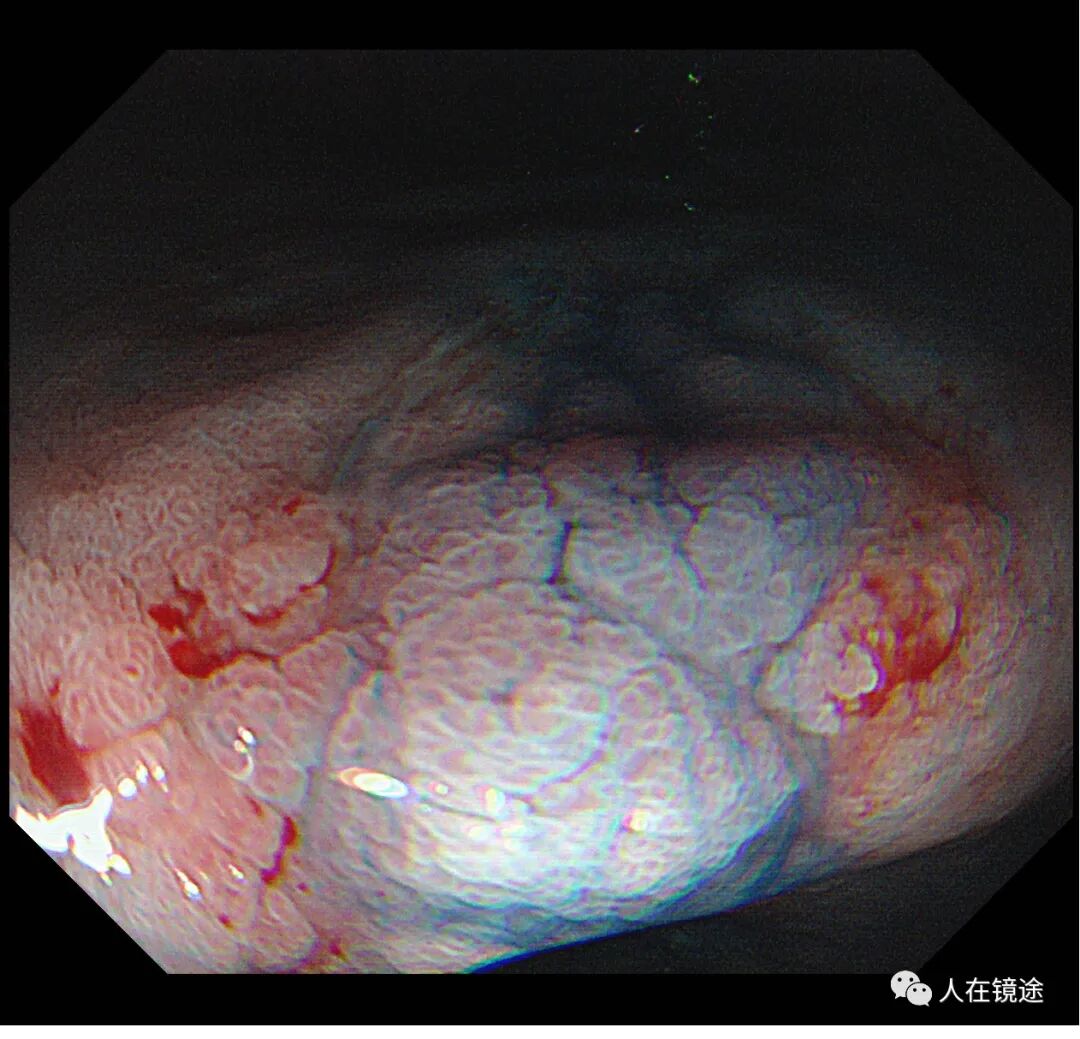

靛胭脂+醋酸示:病变边界清楚,约0.8*1.2cm大小,表面粘膜高低不平,微结构紊乱伴自发性出血,中央见腺管密集不规则,

NBI+靛胭脂+醋酸+近焦示:病变边界清楚,约0.8*1.2cm大小中央见腺管密集不规则伴自发性出血。